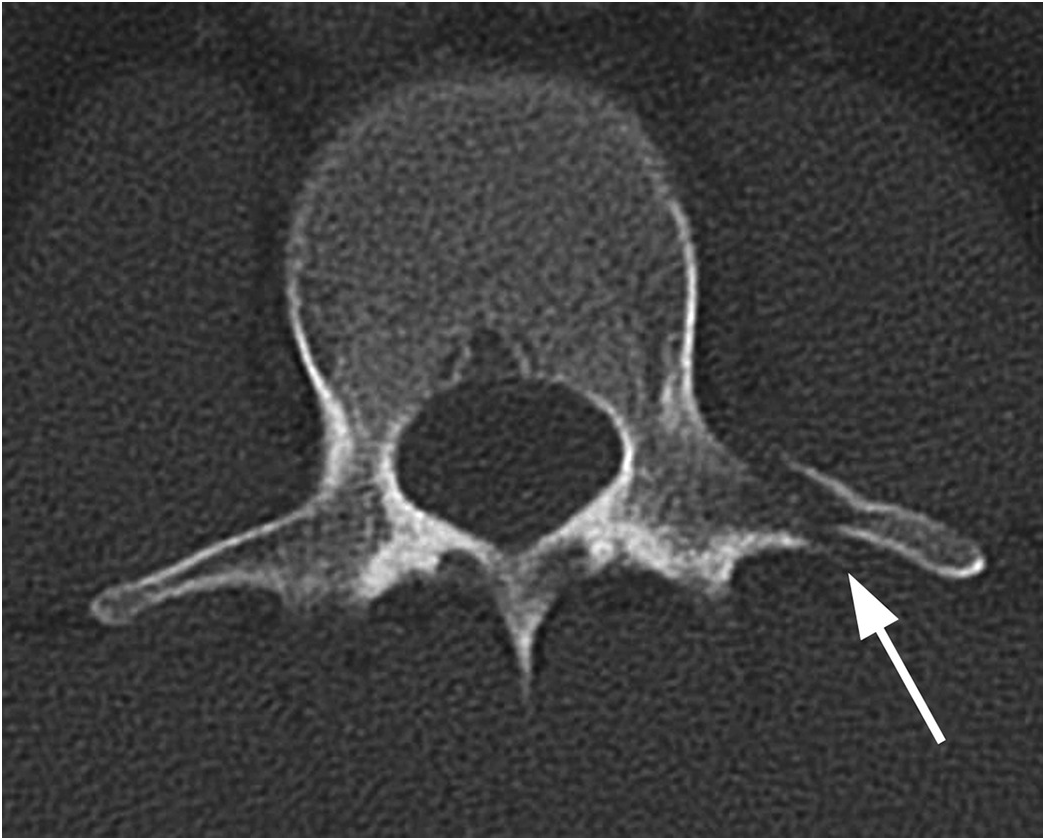

Irregular bone

•vertebrae and hip bones

Osteon definition

structural unit of compact bone

Central (Haversian) canal contains

blood vessels and nerves

Lamellae

concentric rings of bone matric